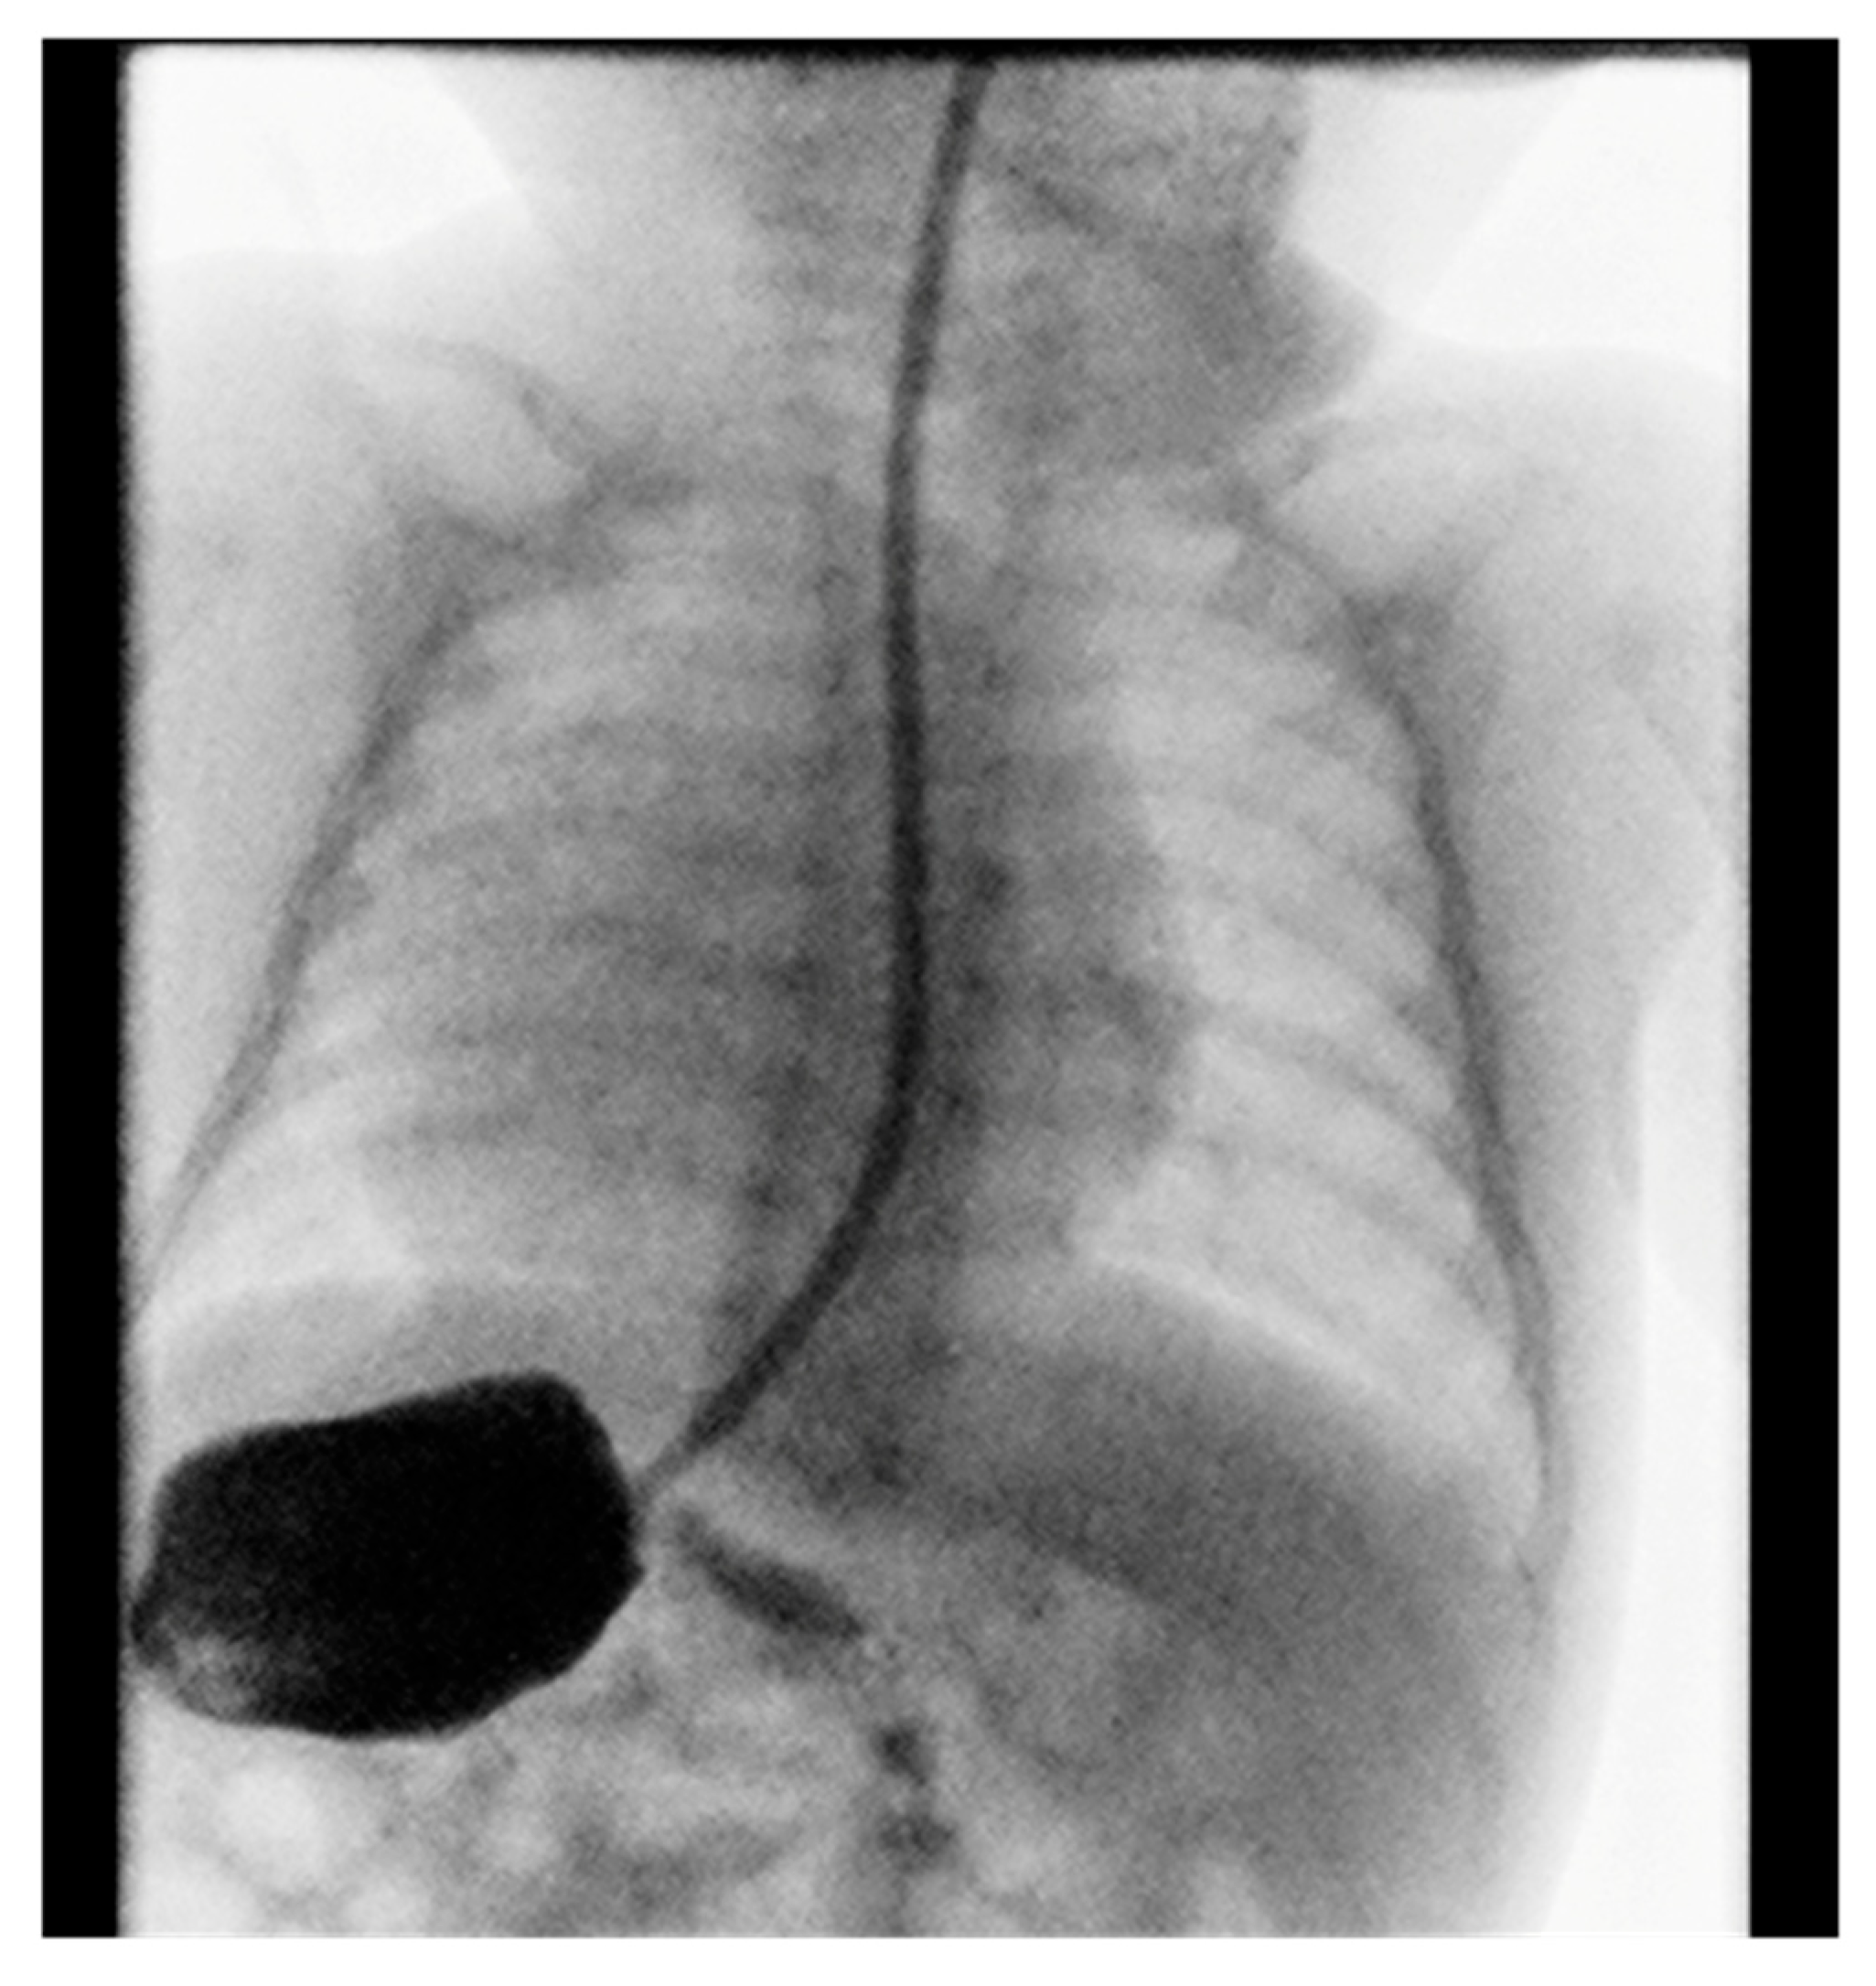

Contrast imaging of the esophagus and stomach shows a normal presentation of the esophagus with the stomach positioned on the right (Figure 2).

Figure 2. Position of the stomach on the right.

Gastroduodenal radiography with contrast showed stomach in the right hemiabdomen. Stomach and duodenum had normal structure and motility. There were no signs of hiatus hernia or gastroesophageal reflux, and there were no obstructions to the passage of contrast fluid.